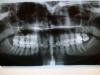

Bier Опубликовано 31 июля, 2009 Поделиться Опубликовано 31 июля, 2009 1. каналы запломбированы не ахти.2. Имеется нависающий край пломбы дистально и патологический карман там.3. Отсутствует нормальный контактный пункт с 7м зубом из-за плохой пломбы (а) и выдвигающегося вниз 7го зуба (б). 7й зуб выдвигается вниз т.к. внизу нет антагониста. З.Ы. если что - то удаление вашего зуба не проблема. И скорее всего никакая пазуха не вскроется. Но мне кажется, если вопросы все с этим зубом решить, боли уйдут. Ссылка на комментарий

muslim Опубликовано 31 июля, 2009 Поделиться Опубликовано 31 июля, 2009 1. каналы запломбированы не ахти.2. Имеется нависающий край пломбы дистально и патологический карман там.3. Отсутствует нормальный контактный пункт с 7м зубом из-за плохой пломбы (а) и выдвигающегося вниз 7го зуба (б). 7й зуб выдвигается вниз т.к. внизу нет антагониста. З.Ы. если что - то удаление вашего зуба не проблема. И скорее всего никакая пазуха не вскроется. Но мне кажется, если вопросы все с этим зубом решить, боли уйдут.Дествительно перепломбировать каналы попробывать нужно ,полечить карман, пломбу поставить в окклюзию Ссылка на комментарий

Bier Опубликовано 1 августа, 2009 Поделиться Опубликовано 1 августа, 2009 это последние снимки? или после них что-то делали?Судя по всему боли из-за кармана между 26 и 27 зубами. Эх, найти бы силы опять пройти все это.За 6 лет уже разочаровалась, столько сделано, а толку ноль.ну вы с какой целью задали вопрос? что мы по интернету решим вашу проблему? Нет, мы можем только дать направление вашим дальнейшим действиям. На форуме много хороших врачей, обратитесь к тому, кто вам больше нравится. Ссылка на комментарий

АНРОША Опубликовано 1 августа, 2009 Поделиться Опубликовано 1 августа, 2009 каналы в 6 зубе перелечивать, потом протезировать (вкладка+коронка), найти пародонтолога, который сможет разобраться с карманом Ссылка на комментарий

доминика Опубликовано 1 августа, 2009 Поделиться Опубликовано 1 августа, 2009 каналы в 6 зубе перелечивать, потом протезировать (вкладка+коронка), найти пародонтолога, который сможет разобраться с карманом+1 ,наблюдаться у пародонтолога ,процесс генерализованный ,т.е. затрагивает все зубы сглаженность вершин межальвеолярных перегородок ,и кость очень порозная ,возможно нужна консультация эндокринолога ... Ссылка на комментарий

Scrabble Опубликовано 5 августа, 2009 Поделиться Опубликовано 5 августа, 2009 6-ой перелечить однозначно-у эндодонтиста. Пульпит в 7-ом тоже возможен. Ссылка на комментарий

олег1965 Опубликовано 6 августа, 2009 Поделиться Опубликовано 6 августа, 2009 6-ой перелечить однозначно-у эндодонтиста. Пульпит в 7-ом тоже возможен. + поискать второй щёчно-медиальный канал Ссылка на комментарий